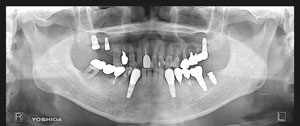

@@R.S‚³‚ñ@56Î —«  ‘åŠw‹³Žö @Žèp“ú@‚Q‚O‚O‚W”N ‚QŒŽ ‚X“úi“yj@㉺Š{  ƒm[ƒxƒ‹ƒKƒCƒhŽg—p@Ö¬“à’ÁÖ@•¹—p@@@

@@@@@ãŠ{  All on ‚U@‘¦Žž‰Ád@@

@@@@@@@@@@@@@ Rpl Tapered Rp  ‚P‚O mm(‚U–{)

@@@@@‰ºŠ{¶‰E@‘¦Žž‰Ád@ ‚R Unit Bridge@

@@@@@@@@@@@ @Rpl Tapered Rp  ‚P‚O mm(‚S–{)@@–ƒWƒ‹ƒRƒjƒAƒNƒ‰ƒEƒ“‚ÅÅI•â’Ô